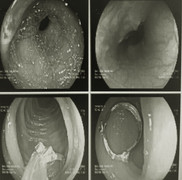

Một phụ nữ bị xuất huyết tiêu hóa, chảy máu và có khối bã lớn trong dạ dày do ăn quả hồng giòn.

Các bác sĩ bất ngờ khi khối bã thức ăn được lấy ra khỏi dạ dày bệnh nhân là hạt xoài, quả chanh leo và đồng xu còn nguyên hình dạng.